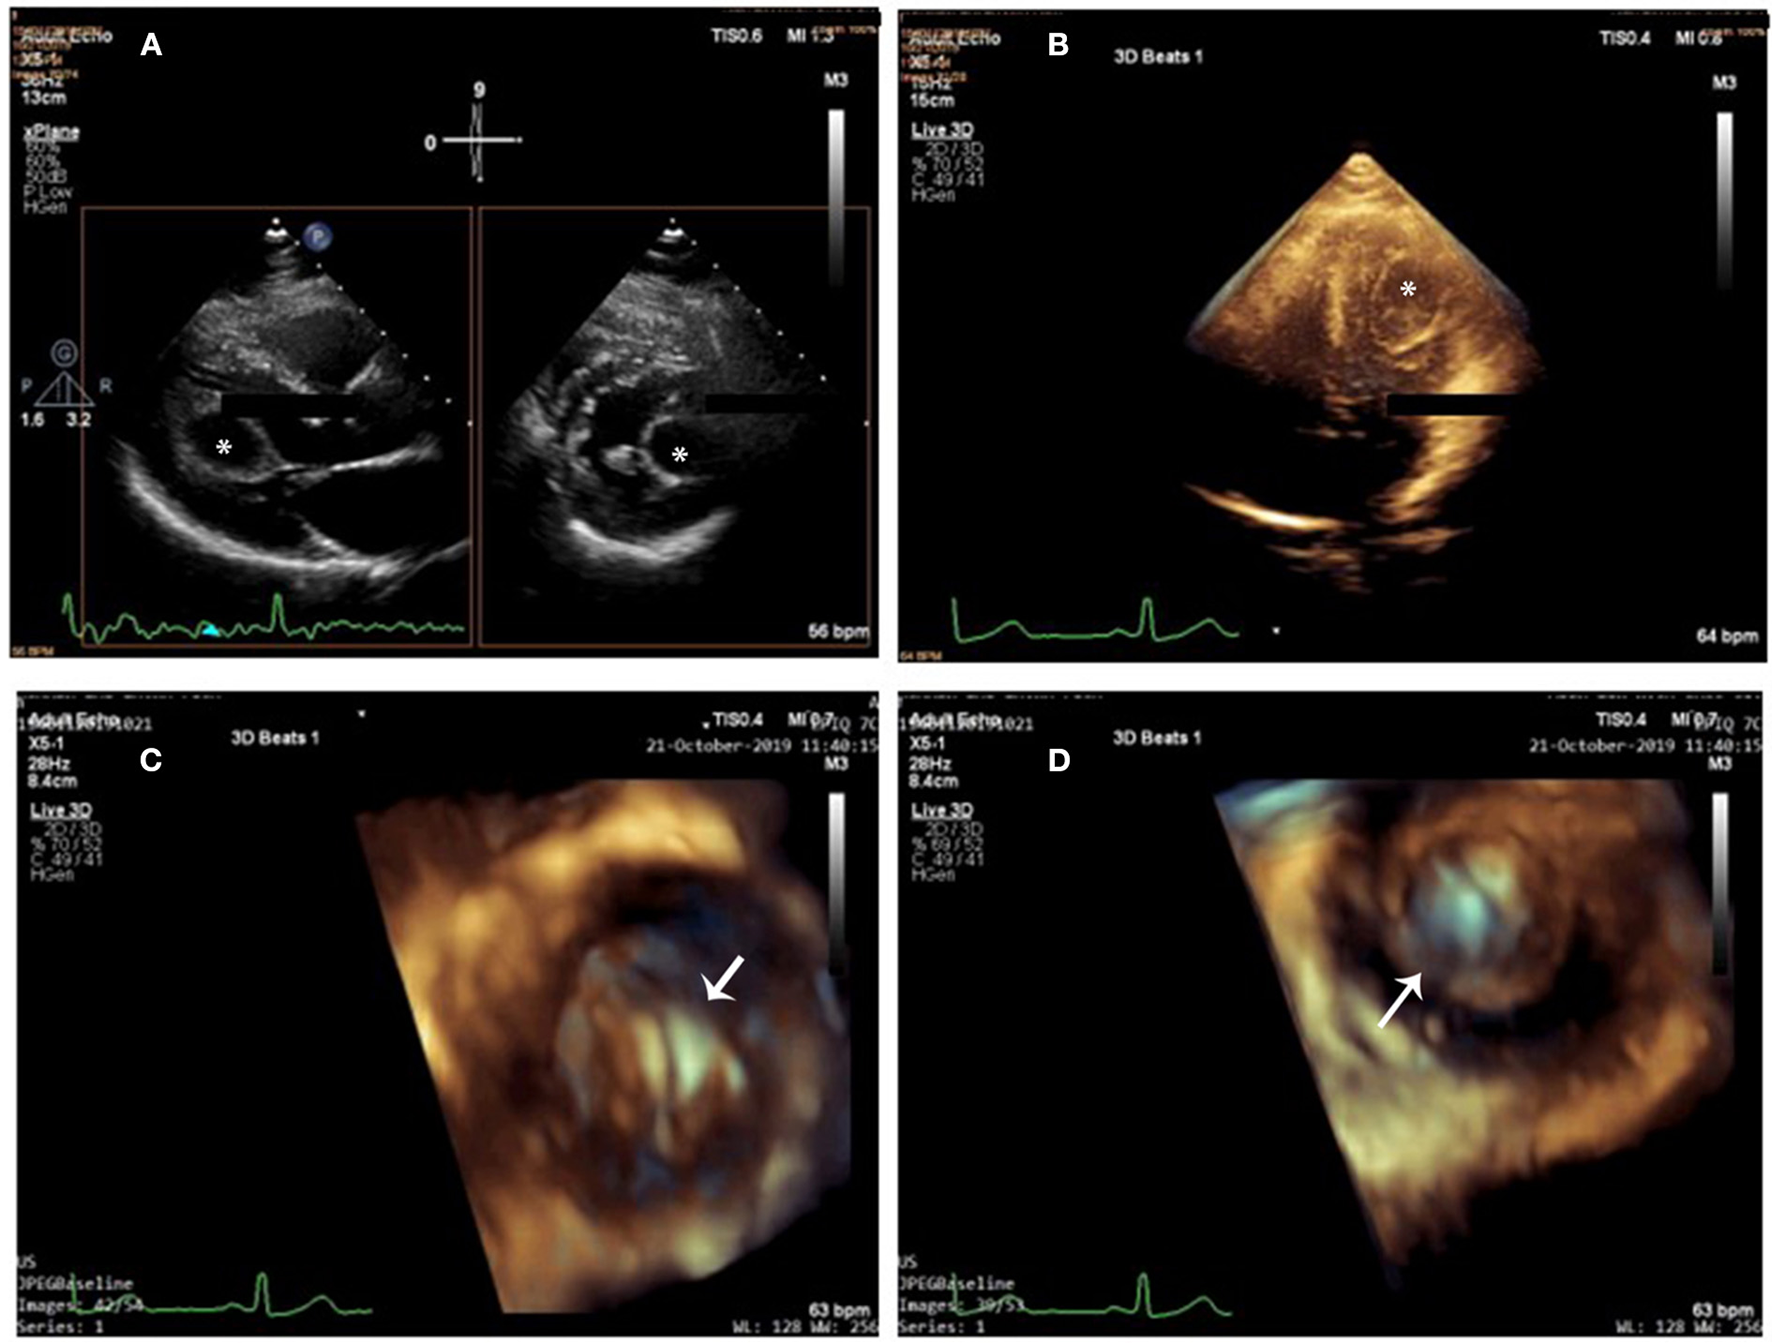

Transthoracic echocardiography (TTE) revealed a drop-like and echo-lucent intramural structure measuring 29 × 21 mm, bulging into the left ventricle from the myocardium of the left ventricular lateral wall and moving synchronously with the cardiac cycle (Figure 1A). On Doppler echocardiography, no color flow was observed within the cystic cavity. Neither the aortic valve nor the mitral valve was influenced by the cyst. The cardiac cyst did not cause intracardiac obstruction. Left ventricular (LV) and right ventricular (RV) dimensions and function and systolic pulmonary artery pressure were normal. These findings were compatible with the patient's clinical functional class (New York Heart Association Classification I).

Figure 1

Cardiac cyst on 2D-TTE and 3D-TTE. (A) 2D X-plane imaging showed a drop-like and echo-lucent intramural structure (star) bulging into the left ventricle from the myocardium of the left ventricular lateral wall. (B) 3D full-volume imaging: The cyst was round and unilocular, with liquid content and well-defined edges (star). (C,D) 3D zoom imaging (en-face view) from outside (C) and from inside (D) perspectives (arrow), the cyst wall looked homogeneously smooth and hyper-echogenic. Cystic sludge was hypo-echogenic.

Three-dimensional transthoracic echocardiography (3D-TTE) was performed to image the cyst in multiple planes. In total three different modalities of 3D echocardiography, including live 3D (narrow-angle), 3D zoom, and full volume (wide angle), were acquired and then cropped to visualize the cyst using “en-face” views. The cyst was round and unilocular, with liquid content and well-defined edges; its wall looked homogeneously smooth and hyper-echogenic when seen from outside and inside (Figures 1B–D and Supplementary Videos 1–3). Cystic sludge was hypo-echogenic. The 3D dataset was used to measure cyst size (28 × 21 × 22 mm), and color Doppler confirmed that it was not vascularized. Enhanced description of the cyst with 3D-TTE helped in the differential diagnosis and aided in the understanding of the surrounding structures. There were no mitral prolapse, no mitral annular dilation, and no mitral regurgitation seen on 3D-TTE.